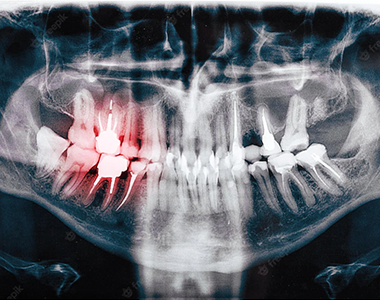

X-rays can show decay that may not be seen directly in the mouth: for example, under a filling, or between the teeth. They can show whether you have an infection in the root of your tooth and how severe the infection is.

In children, an x-ray can show any teeth that haven’t come through yet, and show the dental team whether there is enough space for the teeth to come through. In adults, it can show any impacted wisdom teeth that may need to be removed, before they cause any problems.